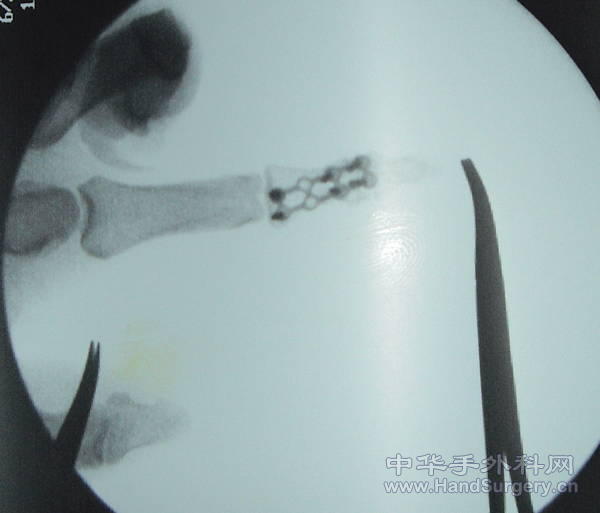

骨折你这样内固定还敢做这个筋膜瓣,真厉害,希望你把术后成活的照片补上来!谢谢!

呵呵,如果你不是选择上钢板的话,可能可以直接缝合了,筋膜瓣加植皮易引起挛缩,另外这个钢板放在这里是不是会影响伸指肌腱的功能啊,楼主应加强随访!皮瓣切取思路不错的,学习了

好像还打克氏针了,得克氏针+可吸收线或钢丝就能解决问题,

支持!这个钢板看着有点怕怕